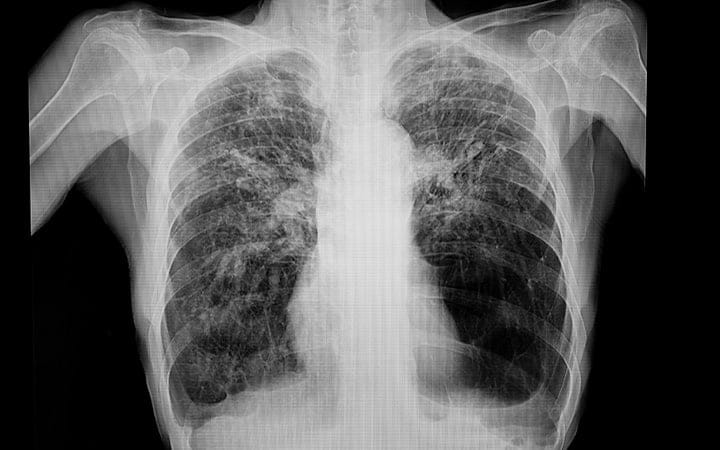

Often referred to as a “spot on the lung,” a lung nodule is an area of dense tissue that shows up as a white spot or shadow on a chest x-ray or CT scan. A recent study of more than 10,000 nonsmokers found the number of people with one or more lung nodule was higher than expected.

“While this is the first study to look for lung nodules in nonsmokers, we already know that chest X-rays and CT scans show one or more lung nodules in about half of all adults,” says Dr. Dunatchik.